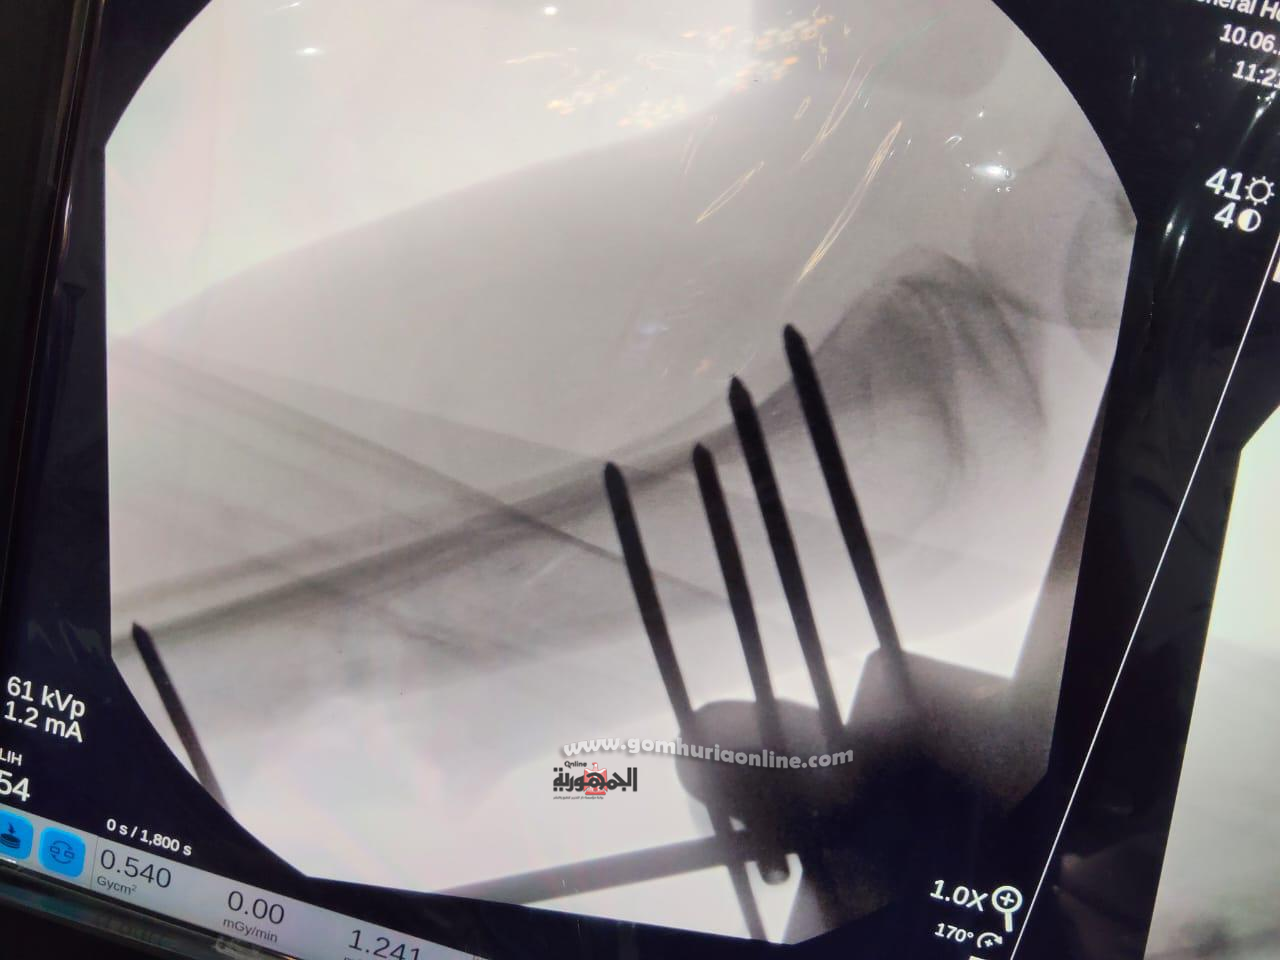

تم تقديم الإسعافات الأولية وتثبيت الكسر مؤقتًا بجبيرة، ثم نُقل المصاب إلى القسم الداخلي للعظام، حيث تلقى الرعاية الطبية والمتابعة لحين تجهيزه للعملية، مع إجراء الغيارات اليومية على الجرح لضمان نظافته حتى لا يؤثر على إجراء العملية، وبعد استكمال الفحوصات، أُدرج على جدول العمليات، وخضع لجراحة دقيقة شملت استخراج الطلق، وتنظيف موضع الإصابة، ورد الكسر، وتثبيته باستخدام مثبت خارجي.

وأشار مدير مستشفى قنا العام، إلى أن العملية نُفذت تحت إشراف الدكتور أسامة رشاد، رئيس قسم العظام، وشارك فيها الفريق الطبي المكون من: د. محمد عبد المجيد الضبع، استشاري العظام، و د. عادل علي، استشاري التخدير ومدير قسم العمليات، و د. فؤاد محمود، نائب العظام، و د. أحمد حسن، نائب العظام وطاقم التمريض بقسم العمليات وقسم العظام .